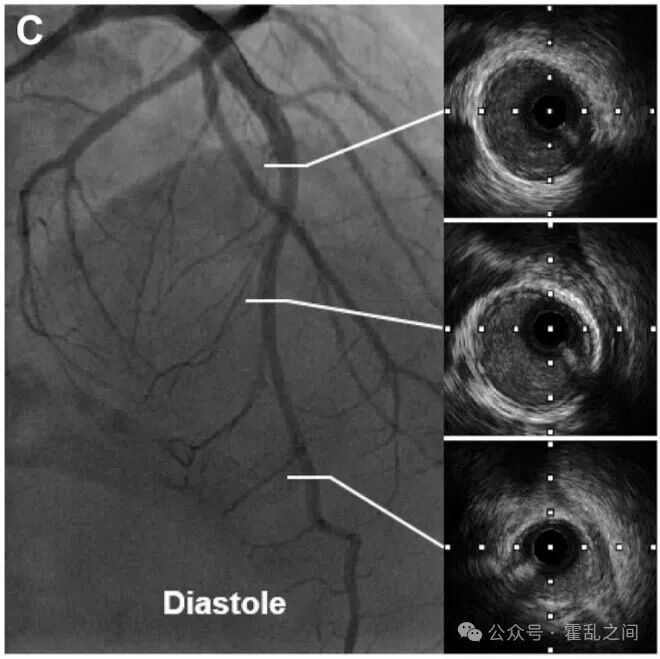

图:舒张期前降支的典型冠脉造影及对应IVUS图像